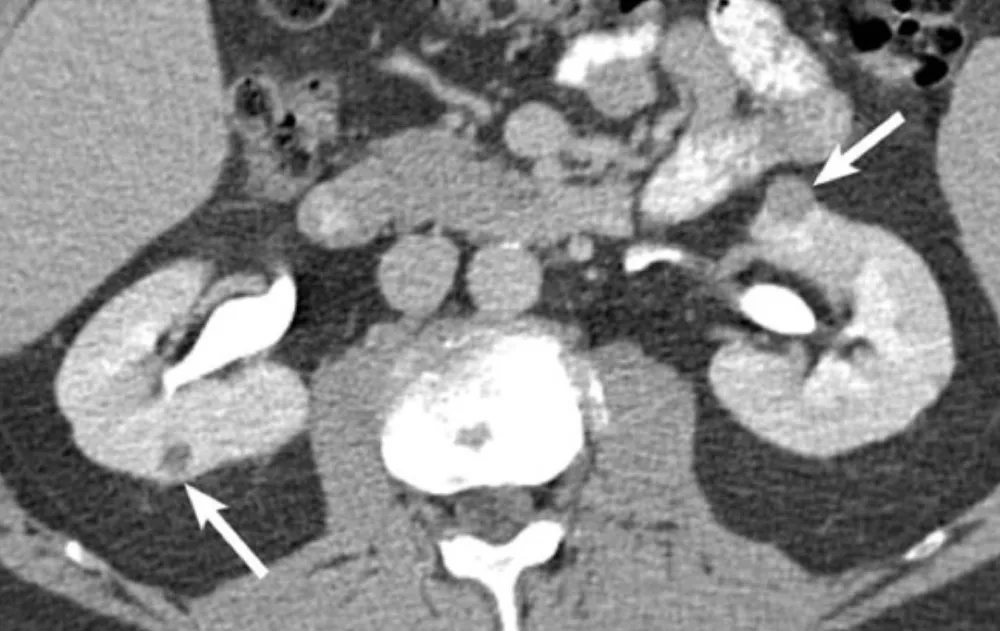

Uma causa incomum de hematúria glomerular intermitente!

Hematúria pós infecção, caso clínicos para auxiliar no entendimento de causas glomerulares comuns e raras...